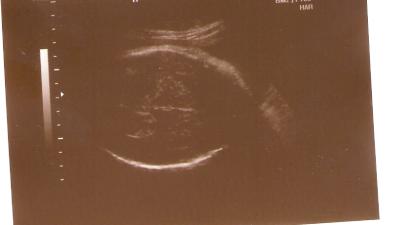

Diesmal gab es nur ein Würmchen Kopf-Durchmesser-Foto, es lag nämlich mit dem Rücken zu uns. Der Arzt meinte allerdings, dass das doch auch mal ein nettes Foto sei, denn so kann man sich ausrechnen, welche Mützen-Größe man kaufen soll ;-)

Damit ihr was sehen könnt, hab ich diesmal halt dann neben dem Würmchen-Kopfdurchmesser-Bild,

auch ein Foto von mir und dem dicken Bauch drangehangen.